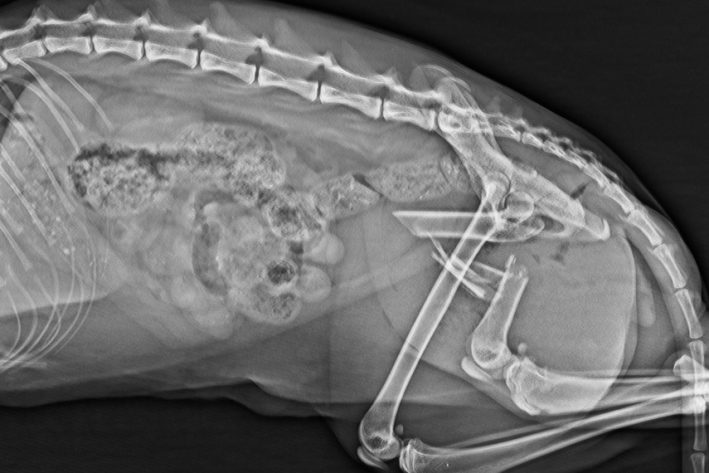

Versorgung einer Femurfraktur einer jungen Katze mit einem externen Fixateur.

Versorgung Femurfraktur

Versorgung der Femurtrümmerfraktur der Katze aus Abb. 1 mit Platte und IM Nagel (Plate and Rod).

Seitliches Kontrollröntgen nach Versorgung Femurfraktur

Seitliches Kontrollröntgen: eine sehr stabile Versorgung dieser sehr instabilen Fraktur.